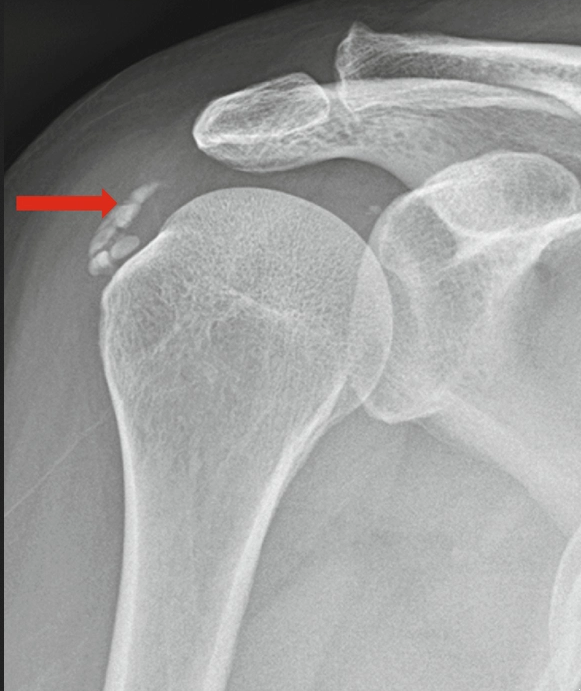

Calcificazione

- Descrizione: Processo fisiologico normale di solidificazione di un osso. Diventa patologico quando i sali di calcio si depositano in differenti tessuti causando la loro degenerazione o distruzione. Può produrre Ipercalcemia (aumento di calcio nel sangue).

- Senso biologico [!]: Calcificare è indurire quella parte. Quando un osso si rompe o diventa fragile in Fase attiva, finisce per calcificarsi più fortemente in fase di riparazione, affinché quella struttura sia più forte e possa sopportare i carichi e superare i conflitti quando tornino a presentarsi. Una calcificazione, dovunque sia, risponderà alla stessa intenzione di "indurire" la zona.